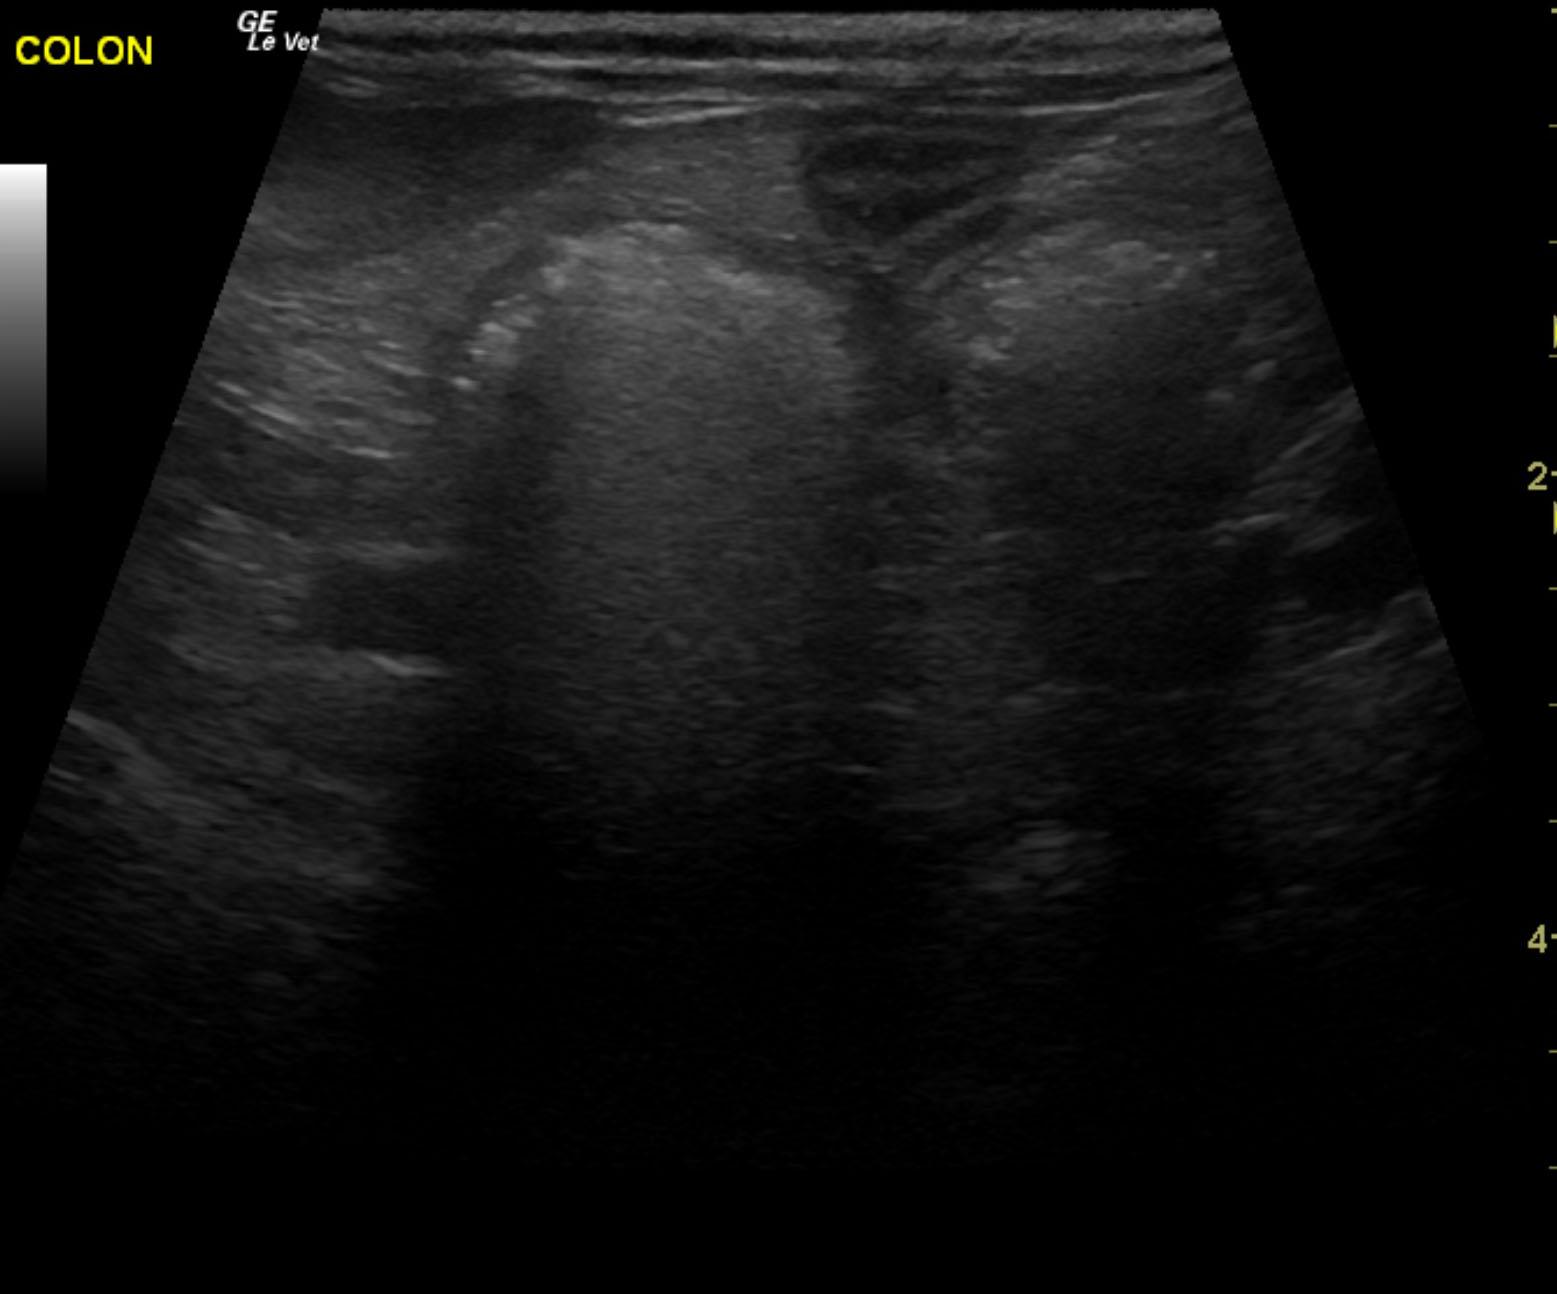

The patient is a 13 year old spayed female Dachshund dog which was presented for four days of anorexia and vomiting. She was given Cerenia, which helped, but still had ileus. Dog has vomited carpet material in past. Spec cPL was normal. Radiographs revealed dilated intestine, which appeared to be colon and cecum.